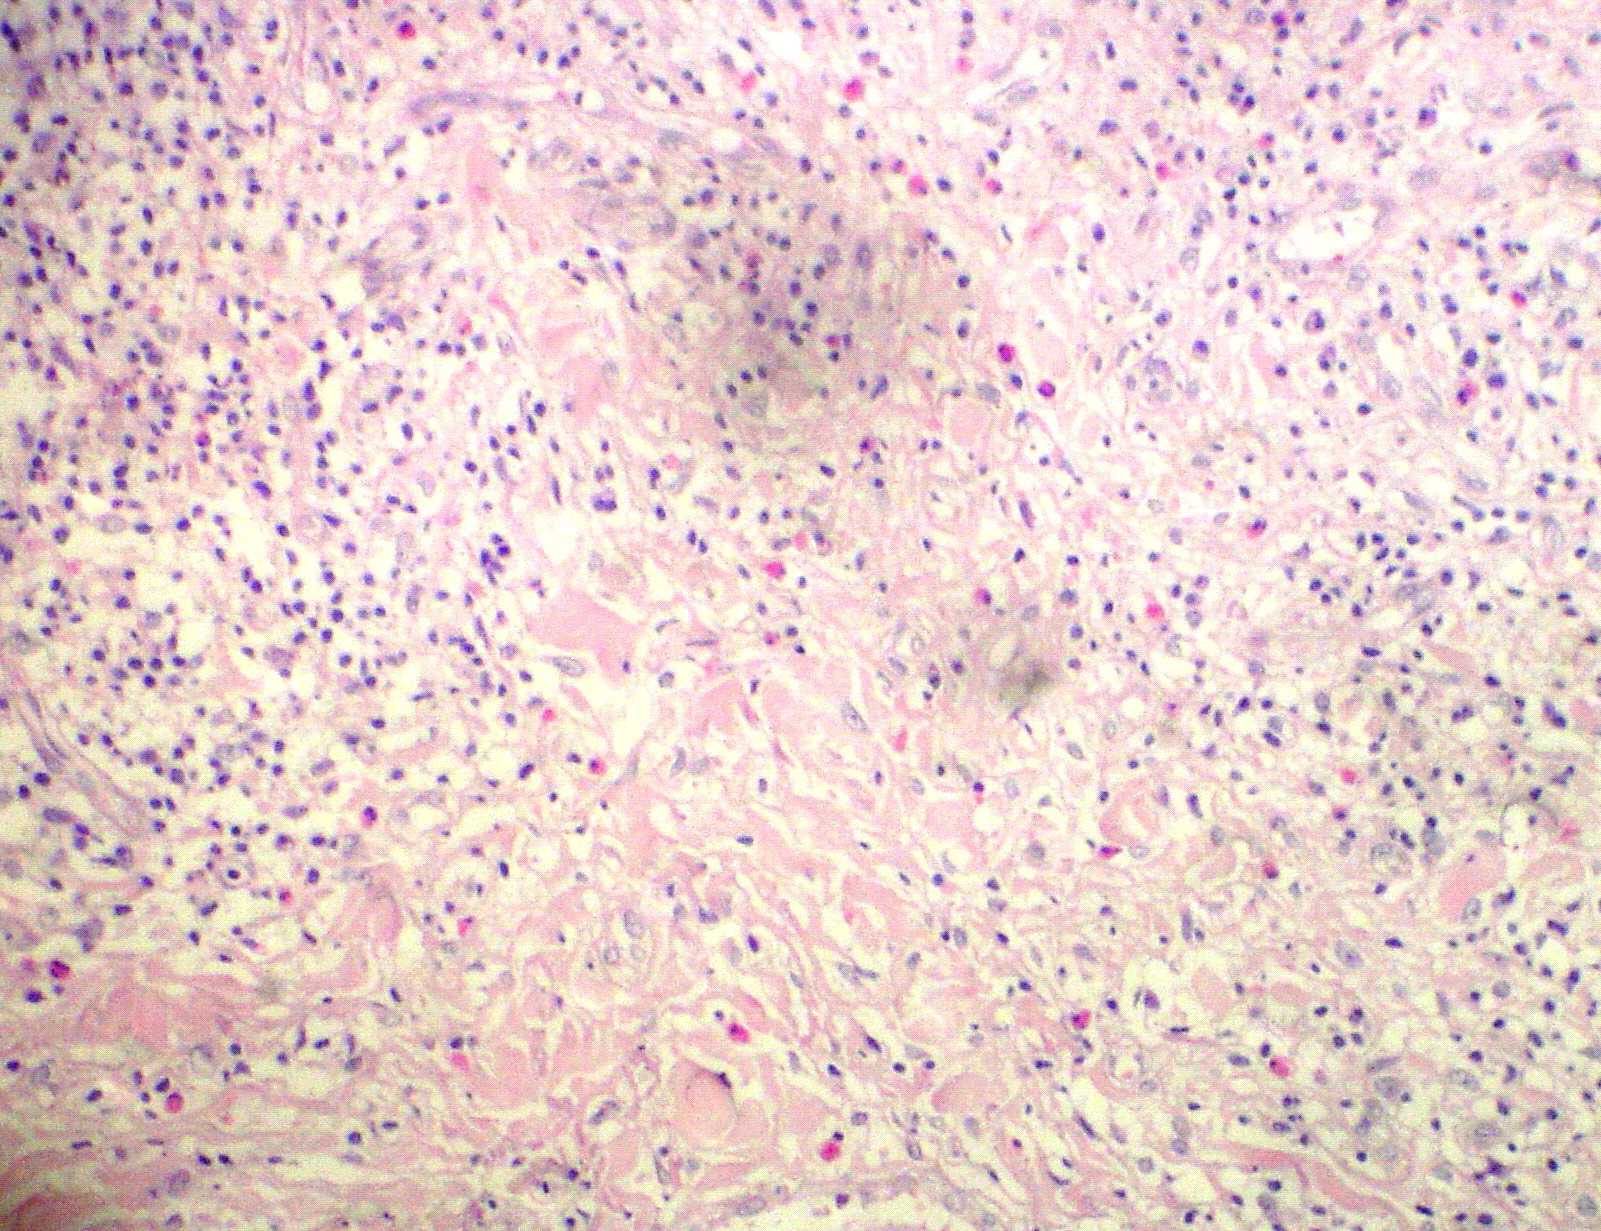

Fig 2: Skin biopsy showed diffuse infiltration by large lymphohistiocytic cells. Some of cells showed lymphophagocytosis [H&E X 12].